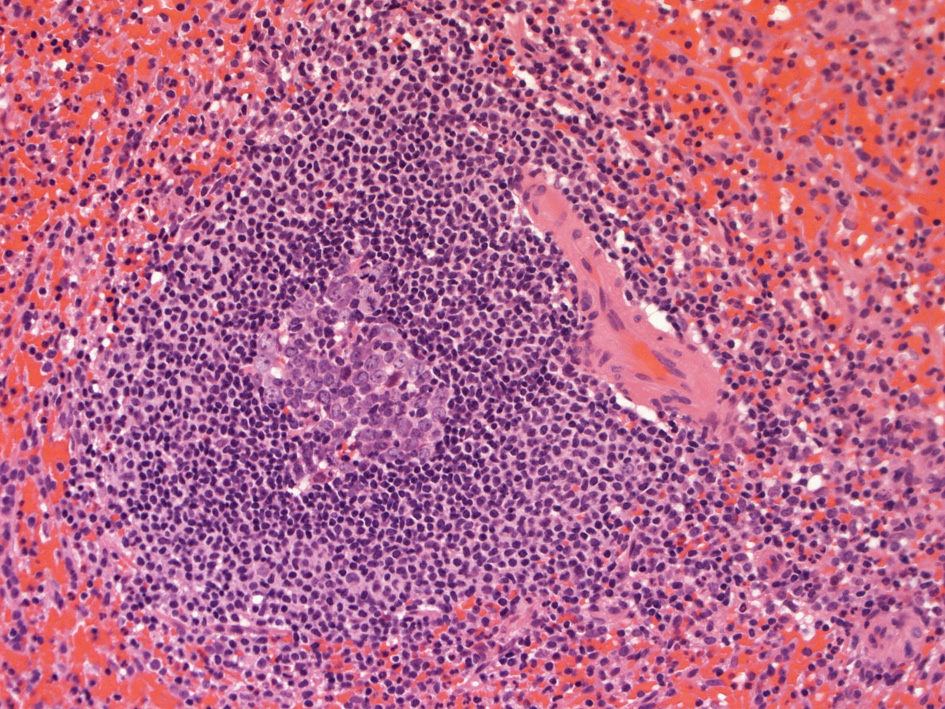

白脾髄の構造 Structure of the white pulp

白脾髄の構造

脾動脈脾柱という結合組織を通って実質内に入るところから毛細血管に至るところまで、その周囲にリンパ鞘が形成され、所々にリンパ濾胞が発達しています。(リンパ鞘=PALSと呼ぶ peri-arterial lymphatic sheathの略)

これらの濾胞内には胚中心が見られることが多い。胚中心の周りには暗調にそまる小型のリンパ球がマントル層を作って取り囲んでいます。リンパ鞘もリンパ節の構造と同じく粗で不規則な細網線維からできたネットワークが骨格となっている。

リンパ鞘はT細胞領域リンパ濾胞はB細胞由来です。PALSのT-cellsは CD4+ cell > CD8+ T-cells

胚中心が多数出現しているときはなんらかの抗原刺激を受けたと考えられる.

慢性感染症がある人の脾臓や特発性血小板減少性紫斑病の人の脾臓では胚中心が特に発達してみられます。一方で自己免疫性溶血性貧血では胚中心は少なく、先天性球状赤血球症ではほとんど見られません。